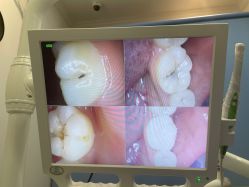

• 南京医科大学友谊整形外科医院

• 全部图片

• 全部图片»

• 效果(1030)»

• 环境(7064)»

• 其他(7)»

• 商户官方图片»